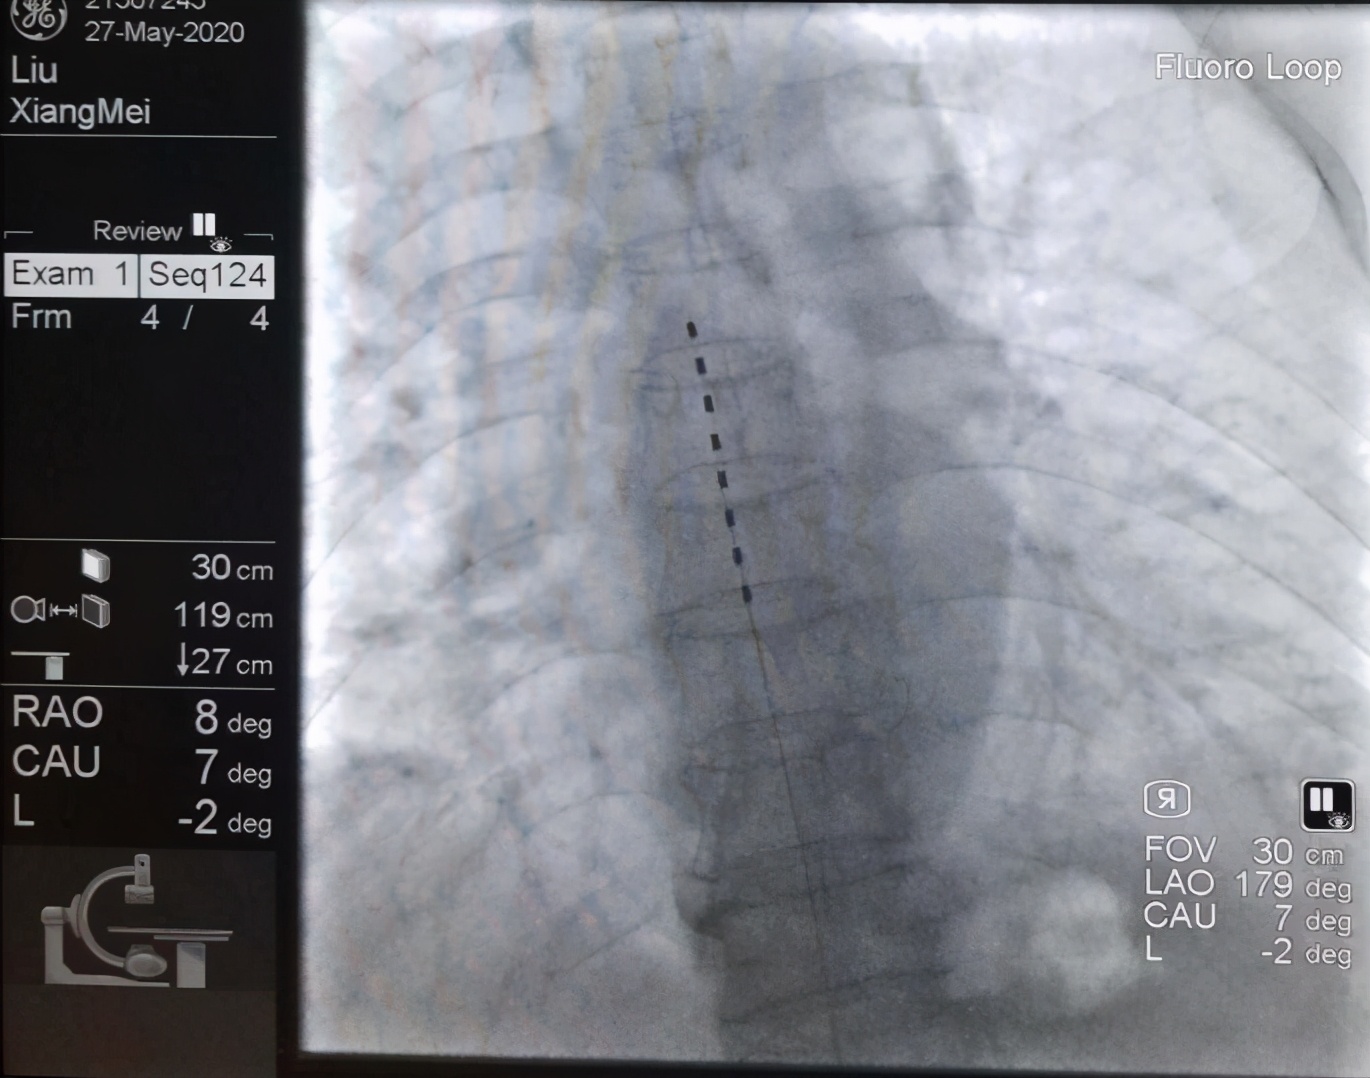

近日,太原市中心医院疼痛科收治了一位62岁的患者何阿姨。两年前,何阿姨因脊柱后凸畸形、腰椎间盘突出症在当地医院行脊柱后凸畸形矫正术(T12-L1、S1椎弓根内固定)。

5.若疼痛无缓解,行脊髓电刺激术(SCS)。

术中,主治医生为何阿姨行L1、L2、L3S神经根脉冲调控治疗,完全复制出疼痛症状。